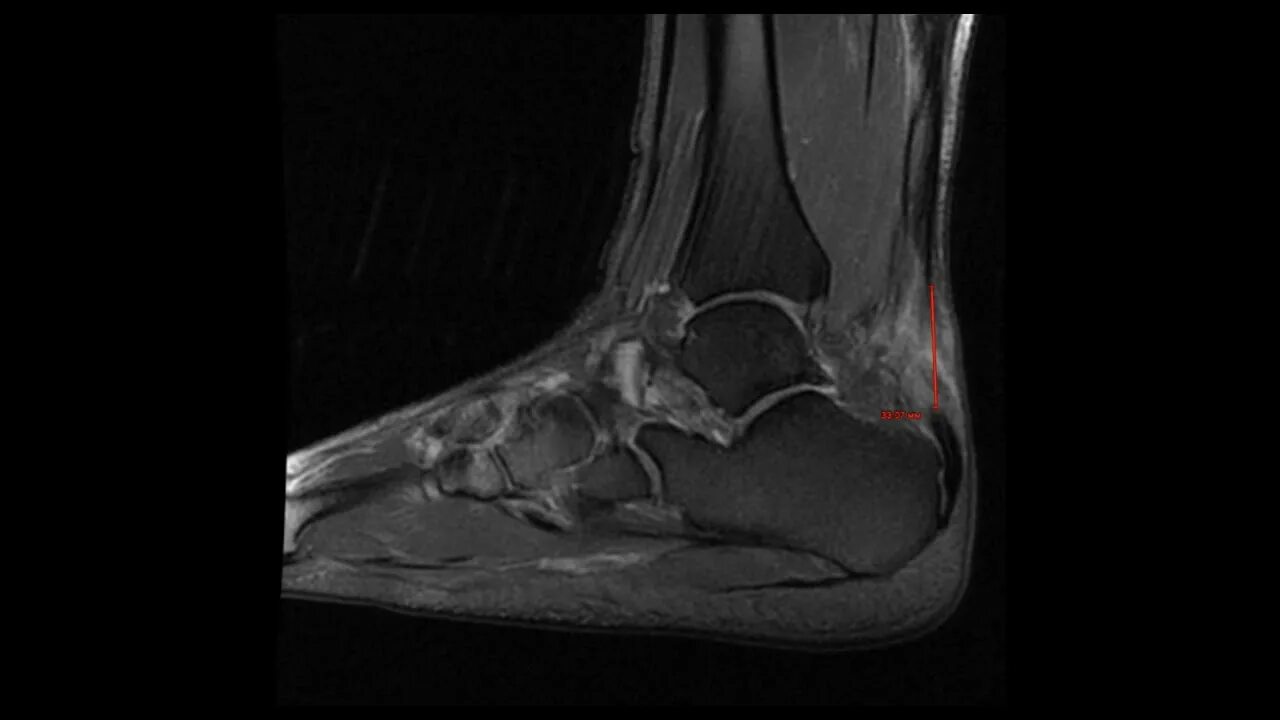

Мрт ахиллового сухожилия